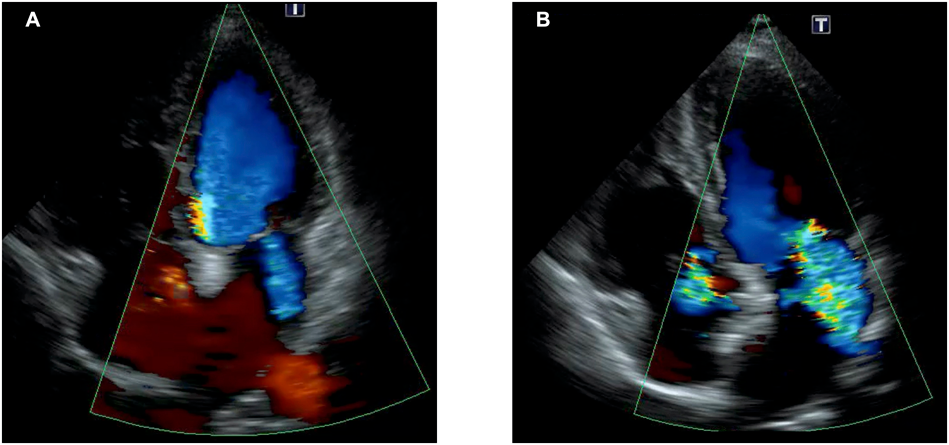

ASD術後には左室への容量負荷を生じ僧帽弁閉鎖不全症(Mitral regurgitation, MR)が増悪する可能性が示唆されている(Fig. 411).経カテーテルASD閉鎖術の前後でMRの増加を認めても予後には寄与しなかったという報告もあるが12),症例毎にMRの増悪については注視する必要がある.なお,術前に中等度以上のMRを伴う症例では,TRと同様に原則として外科的ASD閉鎖術の適応である.

Fig. 4 経カテーテルASD閉鎖術前後でのMRの変化

(A)ASD閉鎖術前では軽度のMRを認めるのみであった.(B)経カテーテルASD閉鎖術には左室への前負荷の増大と右心系の縮小に伴い,MRの増悪を認めたものの,これ以上の悪化は認めなかった.ASD=atrial septal defect; MR=mitral regurgitation